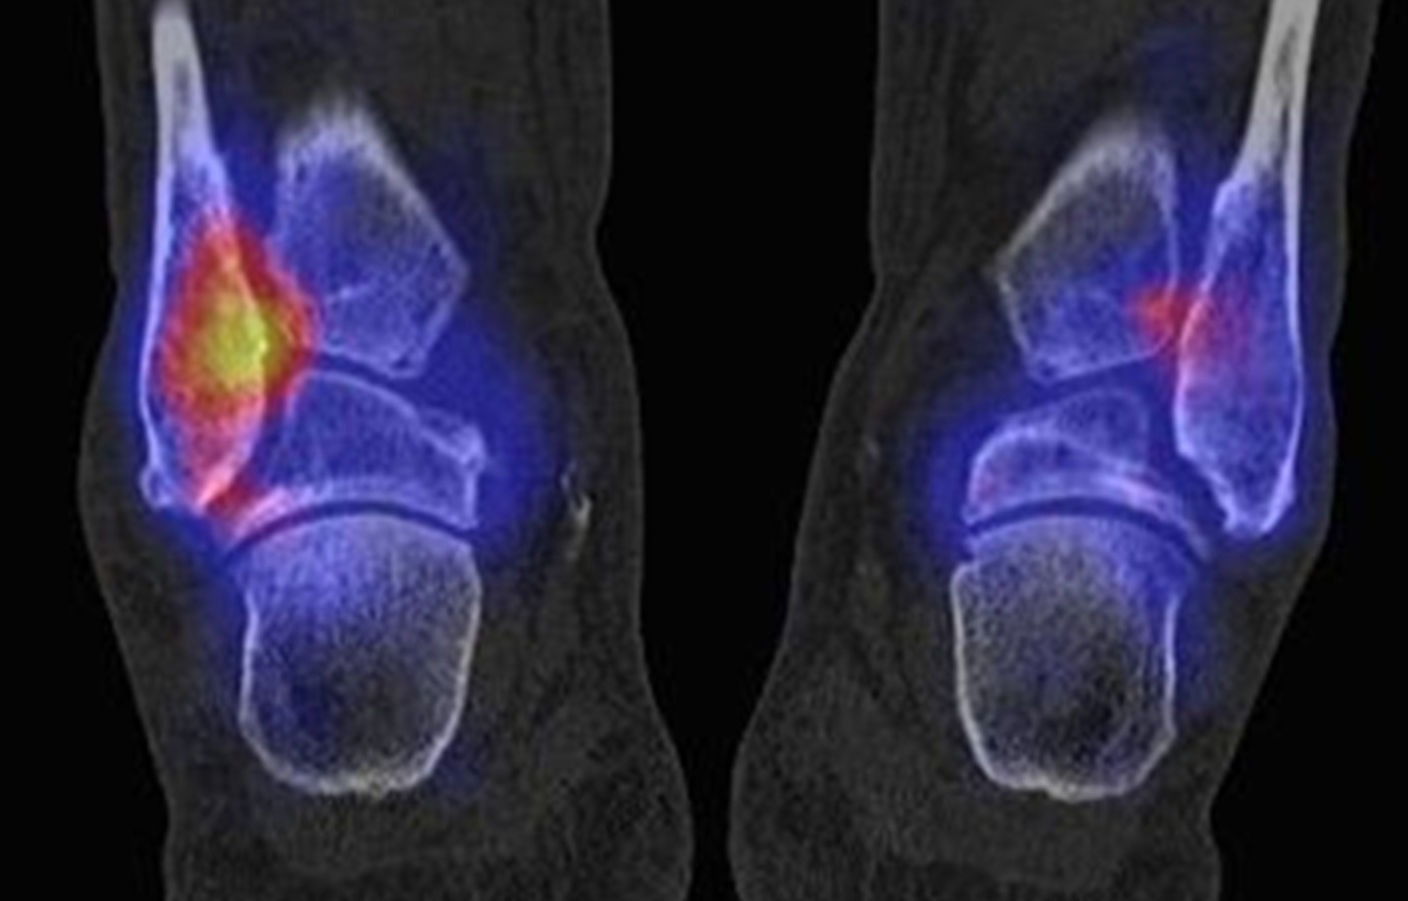

Die Abbildungen 4.2.a bis d zeigen den typischen Aspekt einer talacalcanearen Coalitio. Es besteht nur eine linksseitige, symptomatische Coalitio talocalcaneare (4.2.a und c); das 35 Tage zuvor angefertigte MRT zeigt keine auffälligen Signalveränderungen (4.2.b und d).

Abbildung 4.3. zeigt die Ursache für rechtsseitige Sprunggelenksbeschwerden bei einem Patienten mit talocalcanearen Coalitionen: nur die osteochondrale Läsion an der distalen rechten Tibia ist die Ursache des Schmerzes. Die bilateralen talocalcanearen Coalitionen sind asymptomatisch.